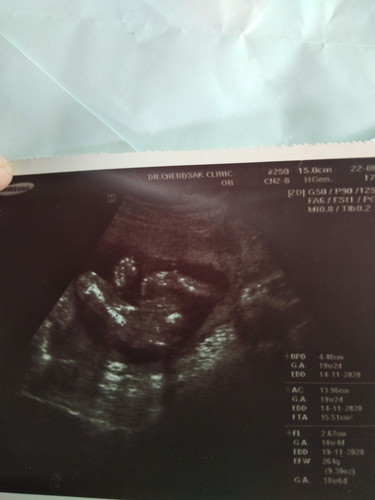

มีใครมองออกบ้างค่ะว่าเป็นผู้ชายจริงๆคุณหมอบอกว่าผู้ชาย100/:แต่เรามองไม่ออก

มองไม่ออกเหมือนกันค่ะ แต่คิดว่าคุณหมอไม่น่าพลาด ผช.ดูง่ายกว่า ผญ. ถ้าเจอหมอเซียนๆดูแค่ลักษณะเด็กก็รู้เลยค่ะ เพราะโครงร่างเด็กแต่ละเพศต่างกัน😊